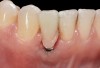

Problem: The implant is placed too facial with significant recession on the midfacial aspect of the abutment and/or crown; the implant is healthy and the patient has a high smile line with an intermediate to thick periodontal phenotype (Figure 1 and Figure 2).17-19

Fig 1. Midfacial recession can affect the esthetics of a smile and lead to an unsatisfactory outcome.

Fig 2. The cause for midfacial recession is excessive labial implant placement. Secondary to poor placement is overcontouring of the implant abutment.